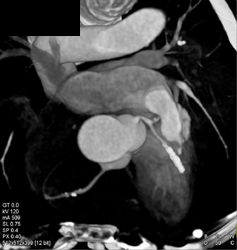

Diagnosis

Ectatic Diseased Aorta and Iliac Aas